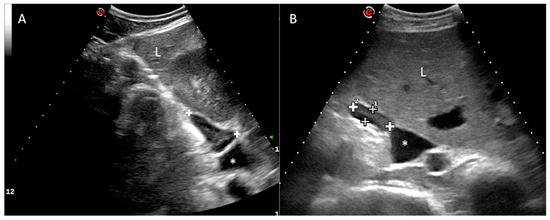

Regarding the right adrenal gland, a longitudinal plane was not consistently obtained, due to the wide footprint of the convex probe that could not easily fit the dorsal aspect of the intercostal space. However, it was possible to locate the transverse plane of the right adrenal gland (with the transducer aligned to direction of the intercostal space). In all of the cows, the right adrenal gland was clearly visualized at the confluence between the right kidney and the liver, immediately adjacent to the caudal vena cava (Figure 2), from the level of the right flank (7/25) to the 11th ICS (7/25), but mainly in the 12th ICS (14/25), of length 3.86 ± 0.56 cm (range 2.76–4.96) and thickness 1.39 ± 0.26 cm (range 0.90–1.88) in the transverse section. The gland length or long axis corresponds to the dorsoventral dimension, while the gland thickness or short axis corresponds to the lateromedial dimension at its maximal point. The ultrasound image of the right adrenal gland revealed an elongated or “L” shape (Figure 2). The caudal vena cava was the main landmark followed during the exploration. Adrenal architecture is commonly distinguishable in the right adrenal gland, with a thin hyperechoic external capsule, a hypoechoic cortex and an echoic medulla. The parenchyma is smooth and homogenous. The vessels and hilum were not clearly defined.

High-resolution images were taken of four adrenal glands (two right and two left adrenal glands) dissected from two dead calves, and the adrenal cortex and medulla were clearly depicted (Figure 4). Internal vessels were identified with a high frequency transducer.

The division into cortex and medulla is evident in gross sections [26], as it is in the ultrasonographic image described in this study, especially for the right adrenal gland in live animals, and is well correlated with the post-mortem specimens (see Figure 2 and Figure 4). As low frequency transducers were used in this study to reach the adrenal glands, the corticomedullary and vessel resolution were not optimal, especially for the left adrenal gland, which is anatomically deeper. This situation is not suitable for obtaining consistent corticomedullary ratios, as described in the literature, to verify reactivity in different zones of the adrenal cortex or medulla [5,6,29]. We have not included specific measurements for the cortex and medulla, and we cannot correlate our results with those obtained in the study conducted by Blutke et al. [5], in which the increase in size and volume of the adrenal glands can be attributed to a significant selective increase in the zona fasciculata in the adrenal cortex. However, although our preliminary findings confirm that ultrasonographic images can discriminate between the cortex and medulla, small vessels can only be identified in the ex vivo image (Figure 4), but not in the in vivo ultrasound, due to low ultrasonographic frequency used and consequently a worse resolution.

Figure 2. Right adrenal gland. Transverse plane of the abdomen obtained at the level of the 12th right intercostal space, showing the right adrenal gland (between cursors or “+” sign) with an “L” shape (A) or elongated shape (B). The medulla can be observed as an echoic internal band. Dorsal is to the left of the image. Caudal vena cava (*). Liver (L). Kidney (K).